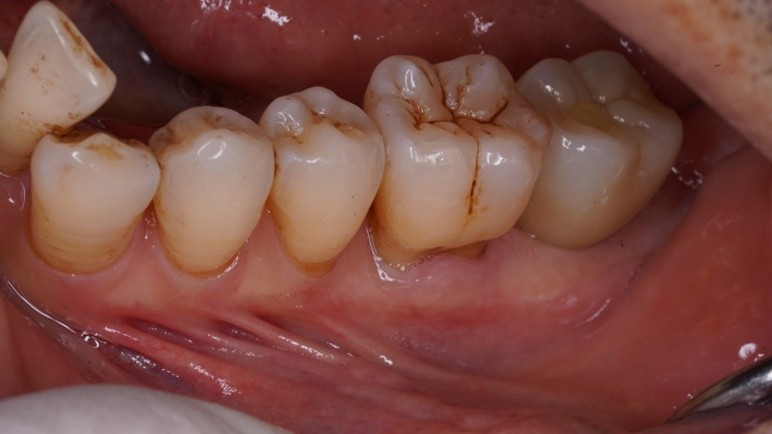

もともと歯が揺れるということで来院された患者様で、検査をすると重度の歯周病でした。当院はインプラントに力を入れていますが「ご自身の歯」に勝るものはありません。外科治療も含めて徹底的な歯周病治療を行いました。

その後にすでに失っていた左下奥歯にインプラント治療をすることになりました。インプラントも歯周病になる(インプラント周囲炎)リスクがあり、インプラント周囲炎は普通の歯周病以上に治療が大変となります。

どのような場合も「まずは歯を助ける」ことを最優先に治療を考えています。